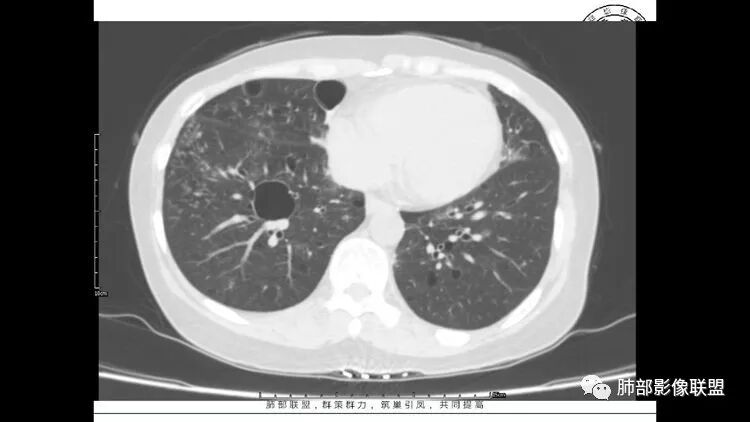

胸CT:1.双肺多发囊性变,以中下肺为主,病变边缘可见肺动脉,部分囊内可见分隔及肺动脉,双下部分肺野周围可见小叶中心结节及树丫征。

2 左肺上叶尖后段 右肺上叶前段 右肺下叶外基底段 结节影,边界清楚,可见柔软毛刺,左肺下叶后基底段混合密度影。

3.纵隔淋巴结肿大?,以主动脉弓为界向上向下增大。

中年女性,双肺多发囊性变,以中下肺为主,病变边缘可见肺动脉,部分囊内可见分隔及肺动脉,左肺上叶较大结节,可见分叶、月牙铲,左肺下叶、右肺中叶磨玻璃病灶,边界清楚,内有空泡,结节,可见尖后段 右肺上叶前段 右肺下叶外基底段 结节影,边界清楚,纵隔淋巴结肿大,

双肺多发散在斑片状磨玻璃密度影及大小不等的薄壁含气囊腔,下肺相对较多较大。双肺多发结节,界清,边缘光滑,分叶不明显。右肺下叶前外基底段散在斑片树芽。前上纵膈偏左侧不规则软组织团块,密度不均,其内可见不规则纤维样低密度,周围簇状小淋巴结。考虑1淋巴细胞间质性肺炎。2考虑纵膈胸腺淋巴瘤。

双肺下叶分布为主的间质改变(磨玻璃影、小叶间隔增厚)、散在气囊影(常有血管贴边)、边界不清小结节